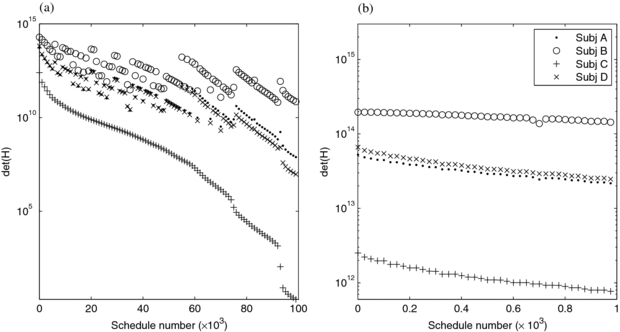

We calculated det(H) and performed Monte Carlo simulations for a range of schedules, infusion lengths and physiologic parameters, with the goal of determining a single schedule applicable to the patient population. We examined the 30-frame schedules in our exhaustive search parameterization, having observed that much of the available det(H) in the entire grid is reached with 30 frames (figure 4) and that 30-frame images are manageable in research and clinical use. Figure 6 shows schedules, ordered in descending values of det(H) for subject C since this had the poorest det(H) therefore is the controlling subject for the robust design. The first schedule thus is the minimax or optimum for the robust design and consists of 29 1 s frames followed by a single, 331 s frame (29×1 + 1×331). In comparing two schedules, generally one which performed poorer for subject C also performed poorer for the other subjects although there are exceptions to this as indicated by jumps in the det(H) curve such that it is not monotonically decreasing. However, focusing on the first 1000 schedules, figure 6(b), reveals that the rank-ordering of the best-performing schedules shows similarities across subjects. That is, many of the best schedules for subject C were also among the best for A, B, and D.

Figure 6. det(H) for the 30-frame schedules, for four simulated subjects are plotted versus schedule number. Schedules are numbered in terms of descending values of det(H) for subject C, so the curves for C descend monotonically while those for the other subjects have jumps. In (a) the top 100 000 schedules are shown. (b) shows a zoomed view of the top 1000. Every 1000th (a) and 25th (b) schedule is shown, for visual clarity.